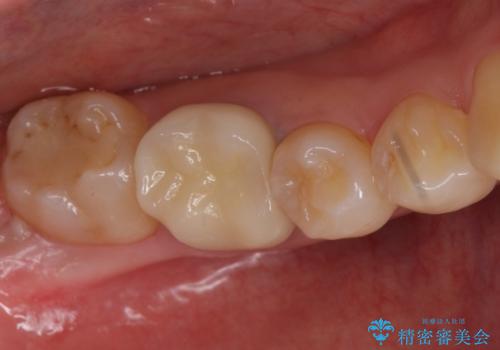

- 右下6 仮歯+セラミッククラウン 11000円+110000円費用は治療当時の料金となります

下の奥歯は口を開くと簡単に外から見えてしまいます。

銀色だった歯が白くなったことで大変喜んでいただけました。